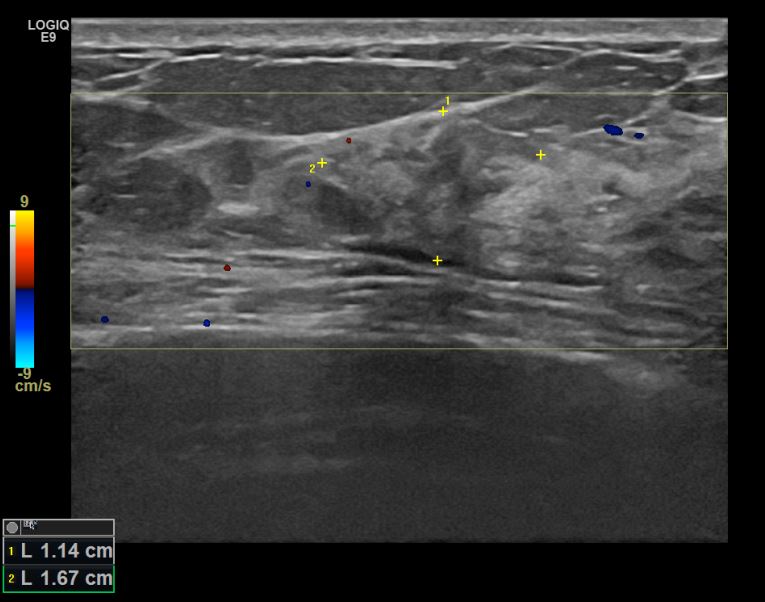

상기환자 우측유방멍울만져지고 유두가 들어간느낌있어 내원하신 60대 여성분으로 유방암 의심혹 조직검사 시행 후 유방암 진단되었습니다.